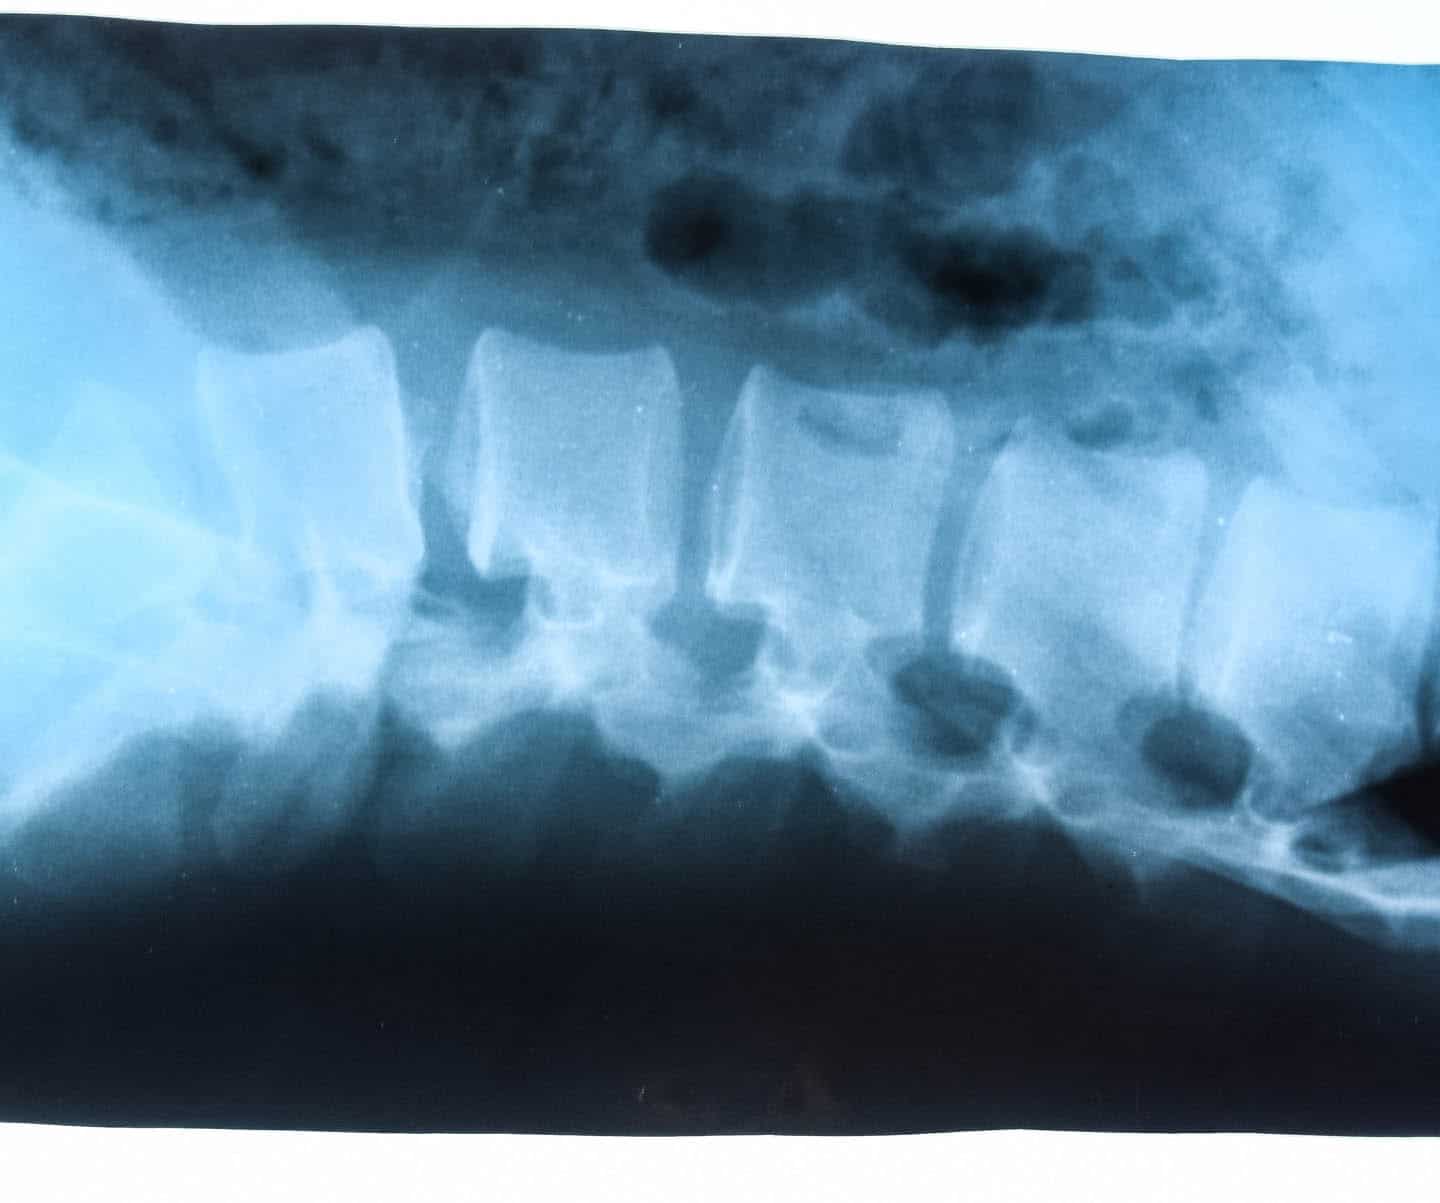

Der Begriff LWS-Syndrom (= Lendenwirbelsäulen-Syndrom) bezeichnet eine Vielzahl von verschiedenen Krankheitssymptomen, deren Ursprung entweder im Lendenwirbelbereich zu suchen ist oder welche die Lendenwirbelsäule betreffen.

Die Lendenwirbelsäule ist sowohl statisch als auch dynamisch sehr großen Belastungen ausgesetzt, deshalb sind Schmerzen im Bereich der Lendenwirbel sehr viel häufiger anzutreffen als in den Hals- und Brustwirbeln.